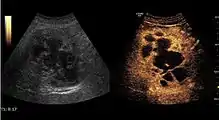

The ultrasound appearance is a well defined lesion, with very thin, almost unapparent walls, without circulatory signal at Doppler or CEUS investigation. The content is transonic suggesting fluid composition. The presence of membranes, abundant sediment or cysts inside is suggestive for parasitic, hydatid nature. Posterior from the lesion the acoustic enhancement phenomenon is seen, which strengthens the suspicion of fluid mass. They typically displace normal liver vessels but no vascular or biliary invasion occurs.

- Hydatid liver cyst. Diagnostic criteria are the presence of membranes and sediment inside.